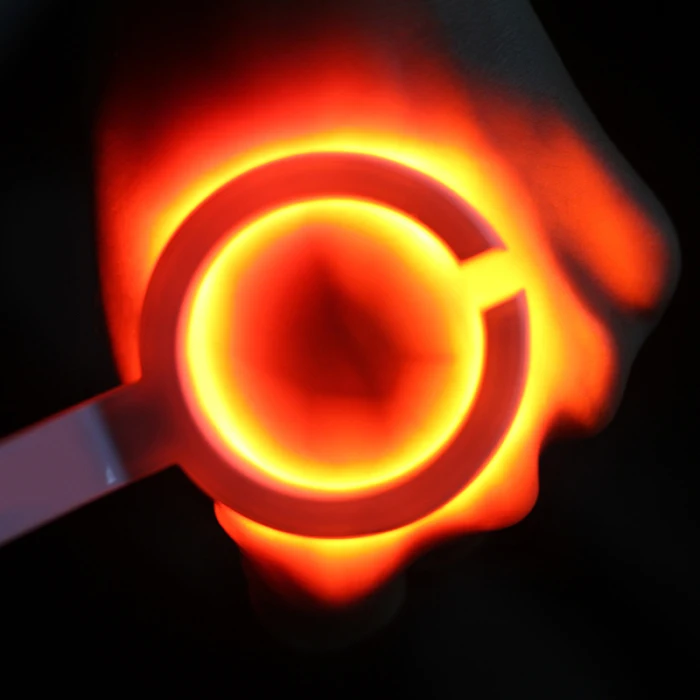

Взрослая детская визуализация инфракрасный васкулярный IV вены Finder Transilluminator вены просмотра TN88

Наше портативное устройство для просмотра Вены-Доступный портативный обнаружитель вен для общего доступа вены у взрослых и детей.

Питание от зарядного устройства непосредственно при использовании с 15 светодиодами, управляемыми одним переключателем.

Он используется для эффективного доступа IV в аварийной медицине.